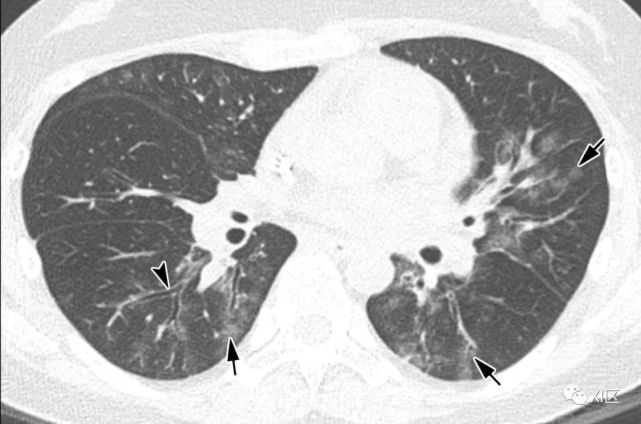

在需要进入重症监护室的重症肺炎患者中,人鼻病毒是最常见的病毒病原体。在重度鼻病毒性肺炎患者中,注意到双侧斑片状实变伴多灶性GGO和小叶间隔增厚

图26 51岁的急性髓细胞性白血病患者,因鼻病毒引起的肺炎,在骨髓移植后3个月出现呼吸困难。

(a)最初的胸部X线照片显示两个肺部均出现不规则的,不明确的斑片状不透明性增加(箭头)。 (b,c)同一天在较低气管水平(b)和两个较低肺叶基底节段(c)上获得的轴向CT图像显示不透明区域不透明,小叶间隔增厚(箭头)和不明确的斑块状GGO( 箭头)。

51岁急性髓系白血病患者,骨髓移植后3个月出现呼吸困难,因鼻病毒引起肺炎。(上) 最初的胸片显示两肺不规则的模糊斑片状不透明度增加(箭头)。在同一天的较低气管水平(中)和两肺下叶基底段(下)轴位向CT图像显示两肺不规则的不透明度增加区域,肺小叶间隔增厚(箭头)和不明确的斑状GGO(箭头)。